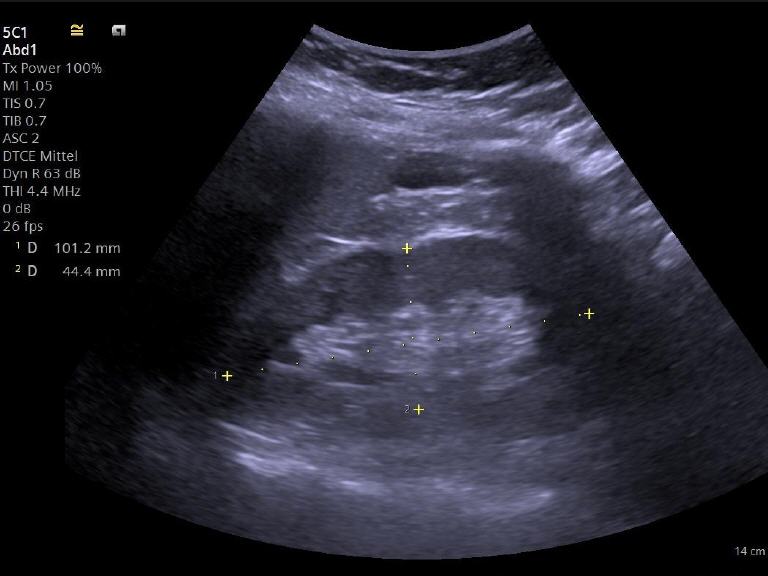

• Sonographiebild einer Niere

Normalbefund – man erkennt gut das dunklere Nierenparenchym mit dem zentralen helleren Nierenbecken.